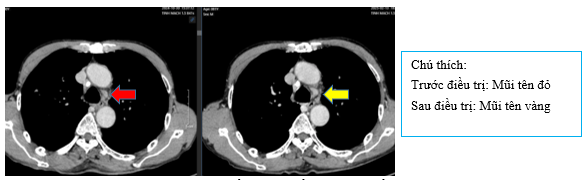

Hình 1:

Hình ảnh chụp CT ngực cho thấyPhổi phải phân thùy S10 có khối ~ 40x30mm bờ tua gai (mũi tên đỏ); thùy trên, thùy dưới còn lại có vài nốt đặc, lớn nhất đường kính 9mm (mũi tên màu cam); Phổi trái: thùy trên có nốt đặc đường kính 3m ngấm thuốc, bờ tua gai (mũi tên xanh lá cây). Nhiều hạch trung thất, lớn nhất ~ 16x12mm (mũi tên xanh dương), có hạch vôi hóa (mũi tên hồng)

+ Chụp CT ngực sau điều trị

Hình 4:

So sánh phim chụp cắt lớp vi tính lồng ngực trước điều trị kích thước khối u thùy dưới phổi phải từ 40x30mm (mũi tên đỏ) sau điều trị giảm còn 26x20mm (mũi tên vàng)